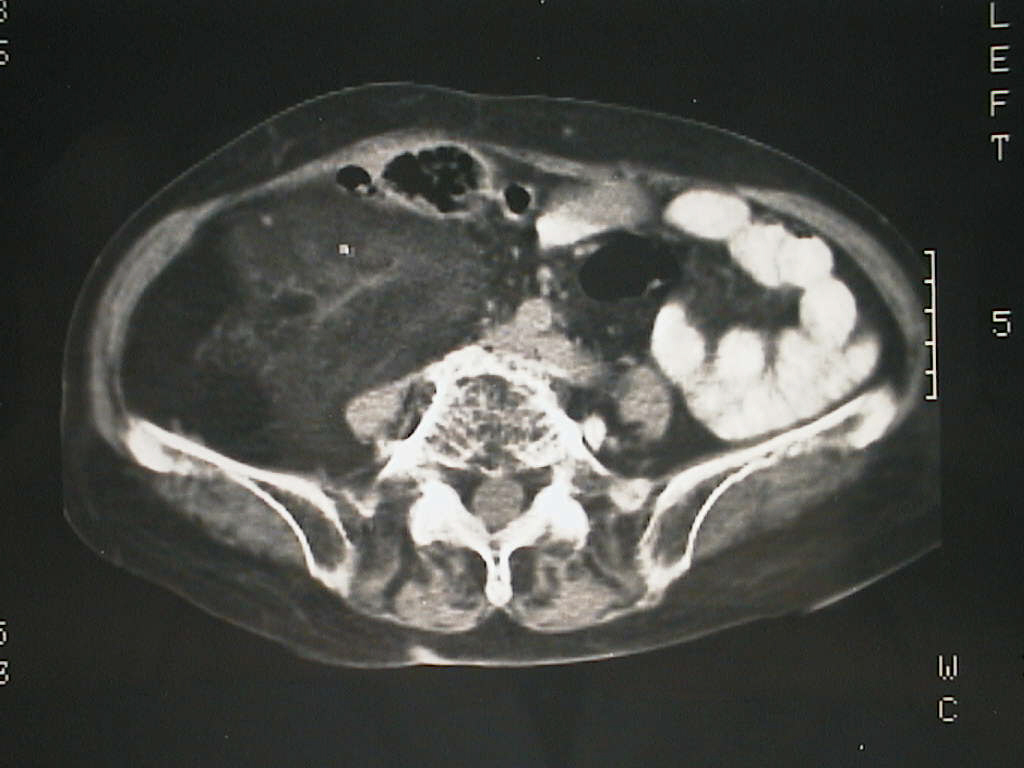

Computed Tomography: large, homogeneous, well-demarcated mass, placed in the right hemiabdomen, without adjacent invasion.

Tomografie computerizată: voluminoasă formațiune relativ omogenă ce ocupă tot hemiabdomenul drept, bine delimitată ce nu invadează structurile vecine.